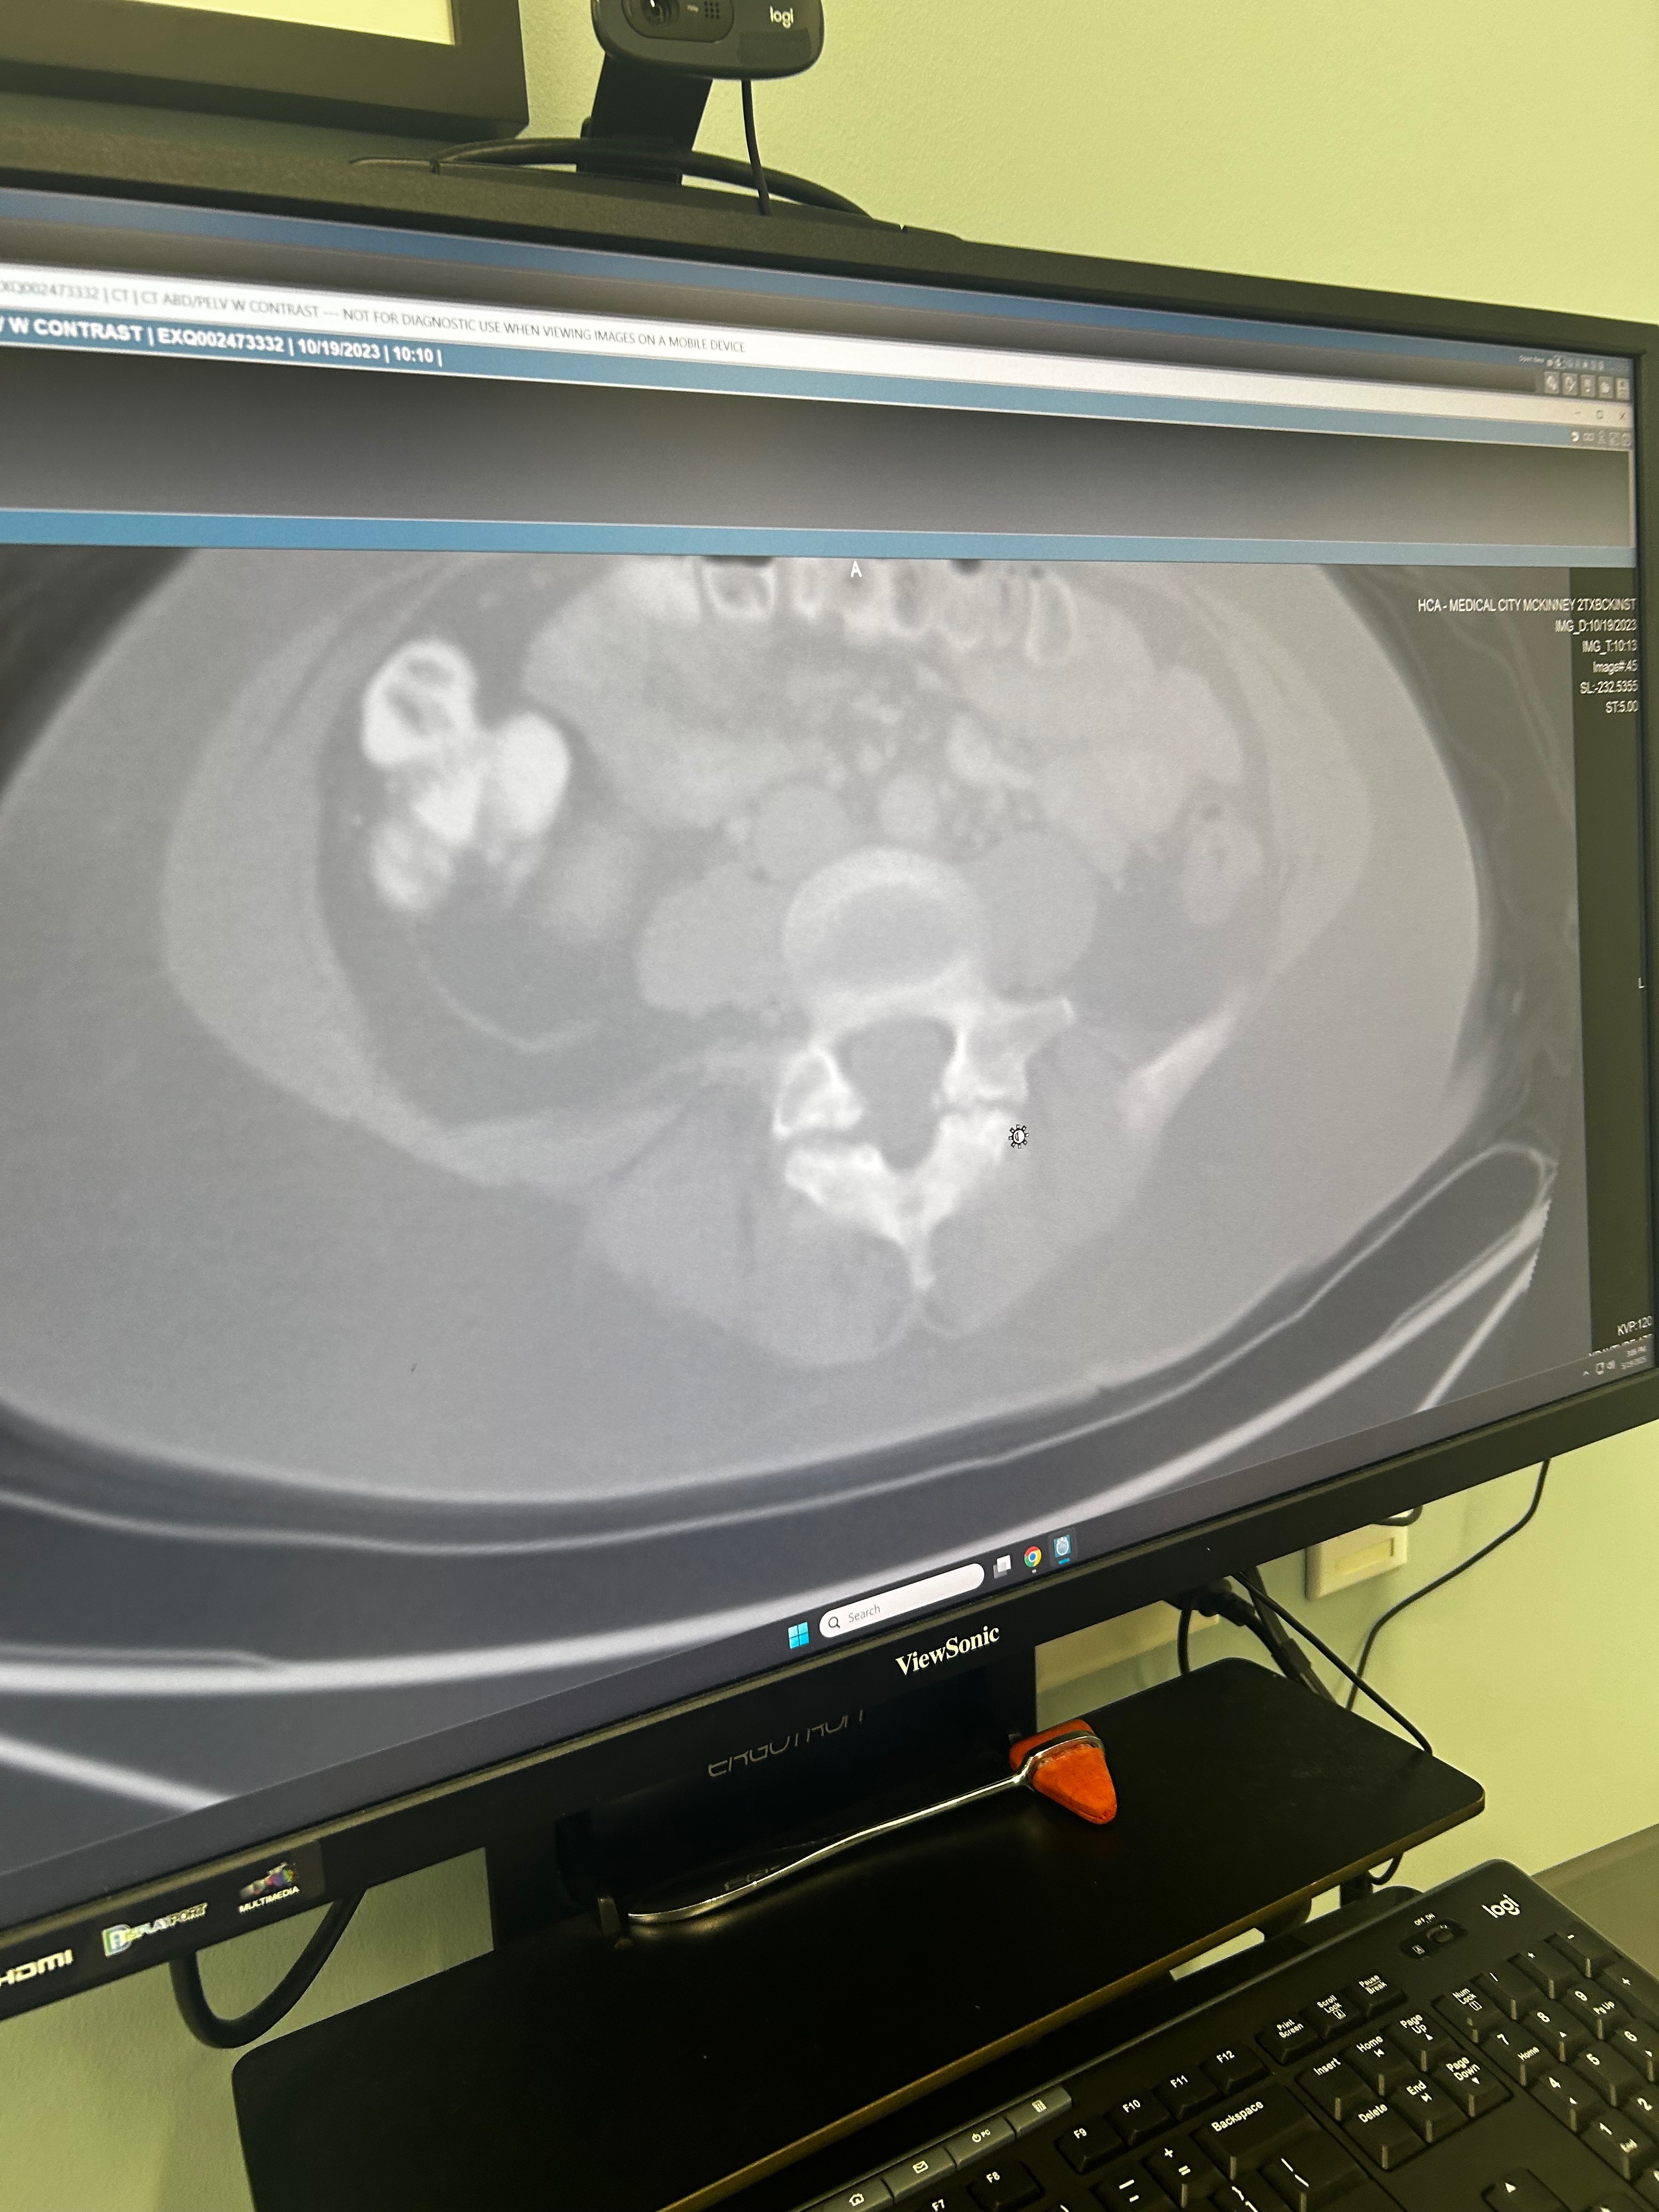

Hello beautiful people, so I’m here to suck up my pride and ask for help! If you know me, you know I’d never ever ask for anything unless it was urgent! Just got off the phone with my MD and the results of my MRI were not good! I need surgery ASAP, as my disc slippage is almost a level 4. That is the most severe it can be! I work 80-100 hours a week to try to do everything I can to save up for this; unfortunately, time is not on my side. I was told today I have to have surgery ASAP and nothing else will help! This would be to help cover my bills while I recover, as it is a 6-8 week recovery time! I thank each and every one of you! I dearly apologize for even having to ask for help!